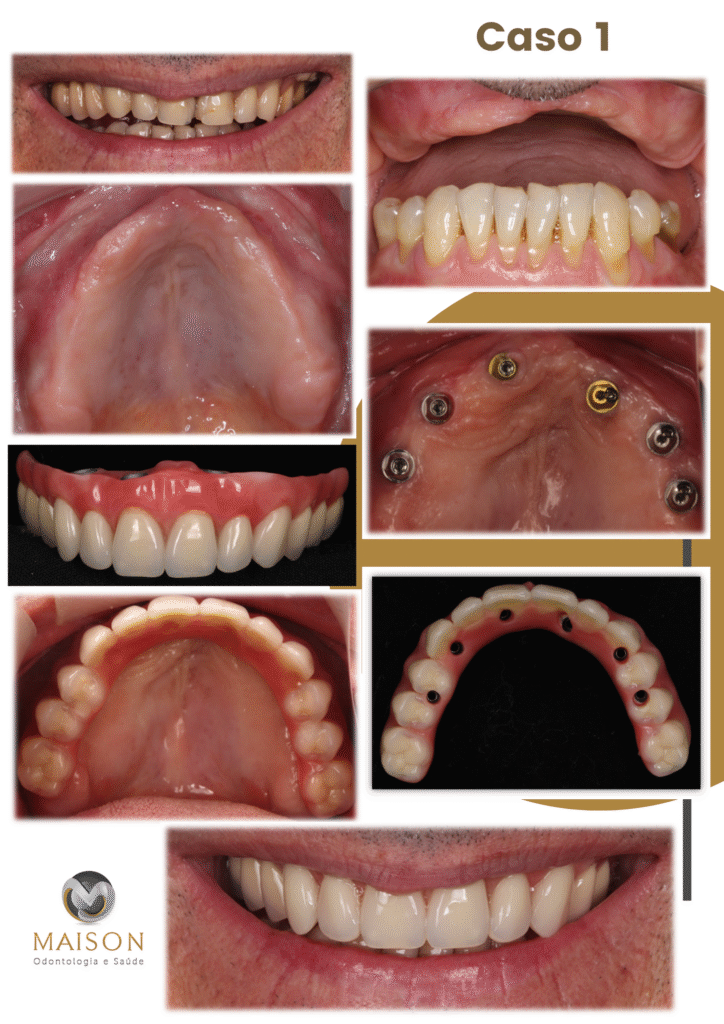

Transformação do Sorriso

Veja o que Nossos Pacientes

25 Anos de Experiência

Transformando Sorrisos

Com mais de 25 anos de experiência na área odontológica, o Dr. Giancarlo, Dra Morgana e equipe se destacam como um profissionais altamente qualificados e comprometidos com a saúde bucal de seus pacientes. Reconhecidos por sua abordagem cuidadosa e profissionalismo exemplar, eles se tornaram referência na área por oferecer tratamentos eficazes e humanizados.

- Técnicas Avançadas de Reabilitação Oral: Implantes Unitários, Múltiplos, Overdenture, Protocolo, Técnica Facco no osso Zigomático; realizamos todos o tipos de próteses sobre implante.